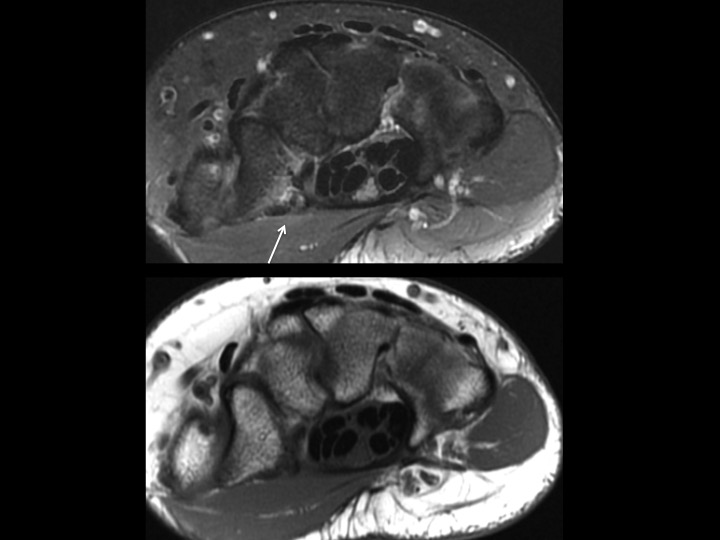

48F pain 2 weeks after fall

Keeping the theme of very subtle fractures. This fracture is easy to miss in the Cor and Sagittal plane unless you recognize the subtle marrow edema at the volar ridge. Cleary visible in the axial plane at the insertion of the transverse carpal retinaculum. These type II avulsions of the trapezium volar ridge may have a tendency toward non-union and may be a source of chronic pain.

trapezium ( RID2193 )